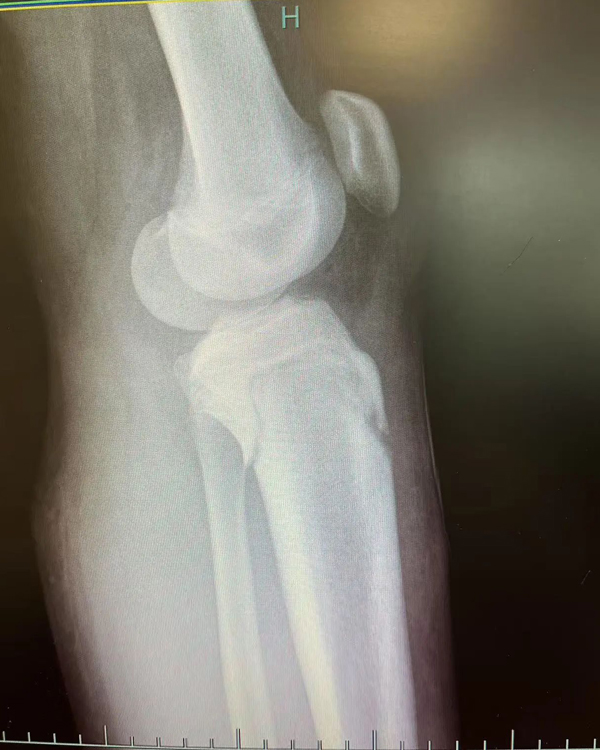

复位前

复位后

进修期间,一段特殊的经历让李刚感触颇深。2月底,一名女性患者因摔伤致左前臂肿痛伴活动受限被送入富阳骨伤医院。通过交流,李刚发现患者竟是家乡同胞,立即用方言安抚其情绪,这位老乡告诉李刚,自己在杭州工作,这次摔伤后先去了别的医院,给出的治疗方案是手术治疗,但听闻富阳中医骨伤医院的中医正骨技术后,慕名而来。经专家团队评估,最终为该患者采用“张氏骨伤疗法”中的手法复位结合杉树皮夹板外固定技术,未开刀便成功修复骨折。